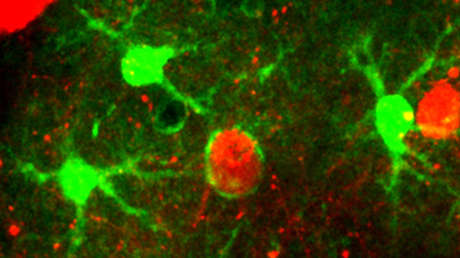

La sucesión de imágenes publicada representa el proceso de limpieza tal y como se desarrolla en el caso de una neurona particular. En ellas se aprecia cómo algunas células contiguas se activan para tragar los restos potencialmente dañinos del cuerpo muerto, mientras que otras se encargan de eliminar las conexiones que la neurona eliminada tenía con otras células.

Un artículo publicado en Science Advances este 26 de junio detalla que los científicos sometieron a los roedores a varias manipulaciones transgénicas para visualizar diversas poblaciones celulares en el cerebro vivo. Además, por medio de una cirugía craneal, les perforaron una "ventana" para acceder directamente al cerebro con la ayuda de cámaras.

Aparte del video, la investigación demostró que tres tipos de células gliales estuvieron involucradas y actuaban de un modo "altamente coordinado". Al tiempo que dos de estos tipos de células engulleron el cuerpo principal de la célula muerta y sus dendritas, el tercero buscó prevenir la propagación de los restos no devorados.